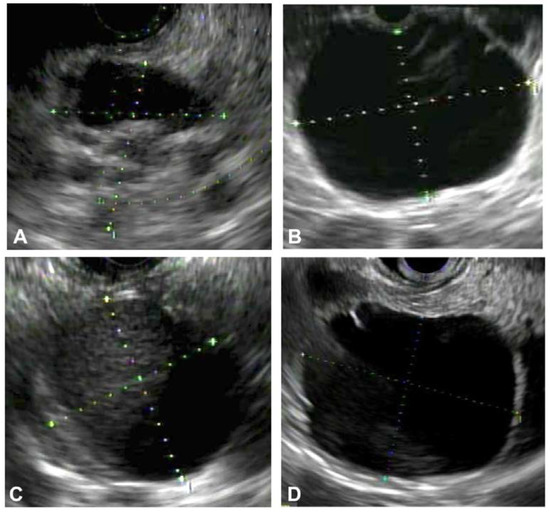

Contrast-Harmonic Mode Endoscopic Ultrasound